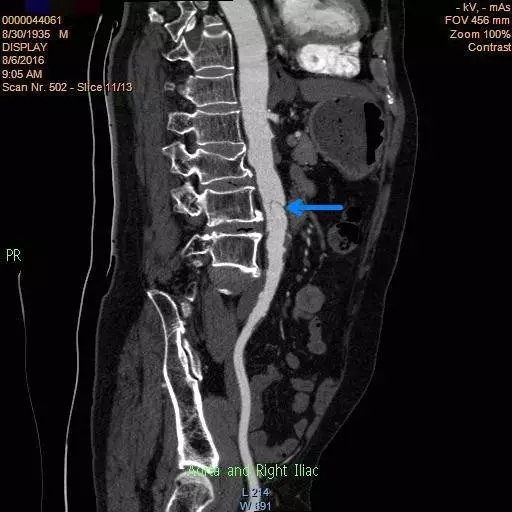

入院后,王兵教授及崔文军副主任医师高度重视,亲自与患者家属沟通病情,告知该病的严重性,并叮嘱患者绝对卧床休息,积极控制血压,保持大便通畅,同时指示主管医师王颖主治医师,积极完善主动脉CTA等检查。考虑到患者病情危重,为避免意外发生,王颖医师亲自陪同患者去CT室检查,CT室也积极配合,开通绿色通道急诊行CTA检查。很快结果出来了:腹主动脉夹层(图1)!同时发现双侧肾动脉狭窄,左侧肾动脉重度狭窄,几近闭塞(图2)。

图1

所幸的是,这次体检发现比较及时,夹层范围也相对较小,但体内的这个不定时炸弹如不尽早解除,随时存在破裂出血风险,主动脉一旦破裂出血,患者九死一生!而肾动脉重度狭窄,一旦闭塞很可能导致一侧肾脏缺血坏死,甚至诱发急性肾功能不全、肾衰的可能!